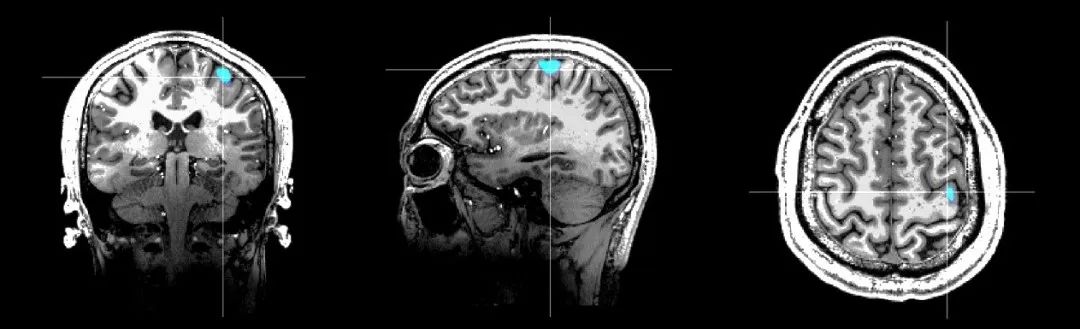

健康人右手运动功能区与7.0T核磁影像融合结果

Marvel MEG®无液氦脑磁图仪是基于完全自主知识产权的新型生物极弱磁场探测技术——原子磁力计研发而成,对脑部磁场的探测灵敏度达到了10fT– 15fT(1fT = 10-15Tesla,地球磁场的十亿分之一)。Marvel MEG®无液氦脑磁图仪以非侵入方式检测和显示大脑神经组织放电活动产生的磁场信号,进行脑功能成像和精准定位。该产品兼备毫秒级的时间分辨率和毫米级的空间分辨率,同时无创、无辐射、无需造影剂,并集成高精度磁场控制系统和多模态刺激系统,可为神经系统疾病的科学研究和临床应用提供无创、精准诊断的手段。这一国产高科技装备早前已获批北京市创新医疗器械,并在北京天坛医院进行注册临床研究。通过对比研究发现,Marvel MEG®无液氦脑磁图仪使常温下实现超高灵敏度的磁场探测成为可能,可解决传统超导SQUID脑磁图的痛点,具备常温工作、无需液氦,无需建设单独的磁屏蔽房,检测效率高等独特优势,大大提升了创新产品的可及性。